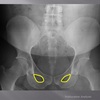

posterior arch of C1

How well did you know this?

1

Not at all

2

3

4

5

Perfectly

10

Q

A

lamina c2-c7